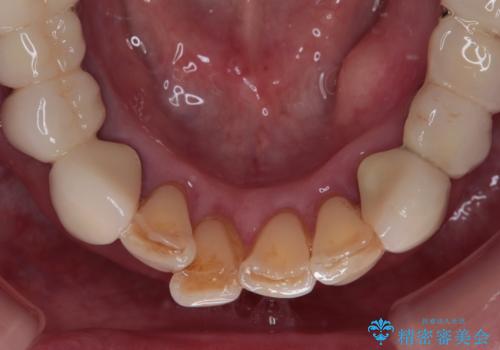

- 歯肉ラインの段差や、歯根が黒く見えている前歯を気にして来院された患者様です。

前歯のインプラントは埋入されたポジションが望ましい位置ではなく、インプラントを活用して段差を回収することは不可能と判断し、歯肉移植によりインプラントを隠して、ブリッジにて歯肉ラインを整えることとしました。

臼歯部の治療も必要と判断されましたが、前歯部を中心とした審美領域をオールセラミッククラウンによる補綴治療を行うこととしました。